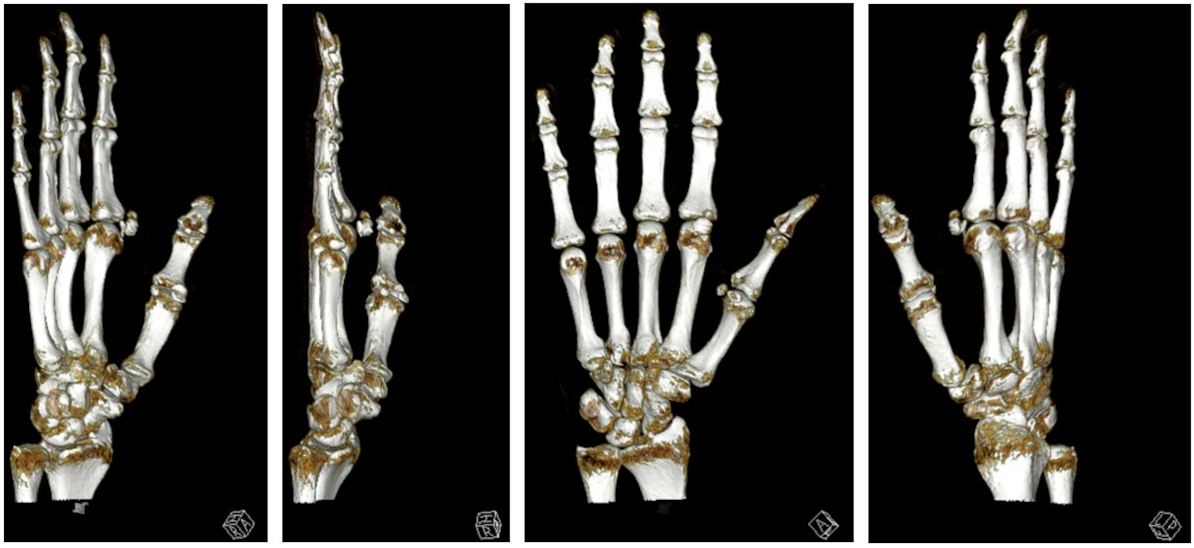

We performed a radiographic examination of the affected hand, followed by a contrast-enhanced CT scan. Based on the imaging findings, avascular necrosis of the sesamoid bone at the MCP joint was suspected (Figure 2 [Fig. 2], Figure 3 [Fig. 3] and Figure 4 [Fig. 4]).

Figure 4: 3D reconstruction of sesamoiditis